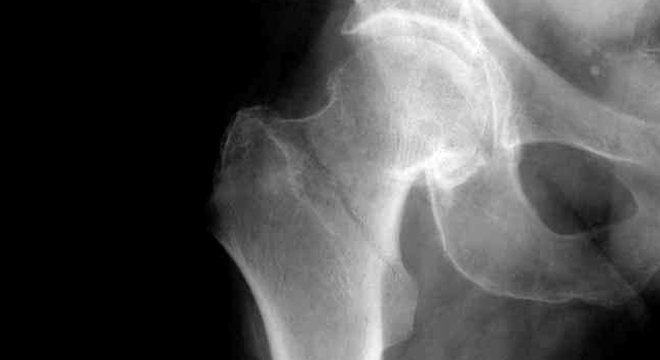

Schenkelhalsbruch: Röntgenbild des Beckens

Zur Diagnose eines Schenkelhalsbruches werden verschiedene Untersuchungen und Abklärungen durchgeführt. Dazu gehören unter anderem:

• Unfallereignis, Schilderungen des Patienten sowie Alter des Patienten weisen den Arzt meist bereits in die richtige Richtung

• Sicherung der Diagnose durch Röntgenbild Beckenübersichtsaufnahme